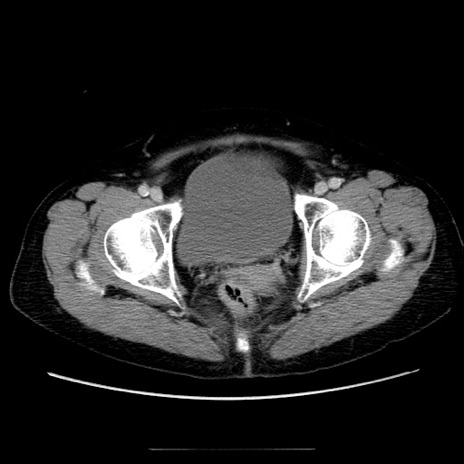

冠状断像

【症例】70歳代女性

【主訴】お腹が張る

【現病歴】1週間くらい前から腹部膨満の自覚あり。昨日夜から増悪したため、本日救急外来受診。

【身体所見】意識清明、BT 36.5℃、BP 165/106mmHg、HR 80bpm、SpO2 98%、腹部:膨満、軟、自発痛・圧痛なし、触診にて不快感あり、腸蠕動音:減弱

【データ】WBC 12600、CRP 1.04